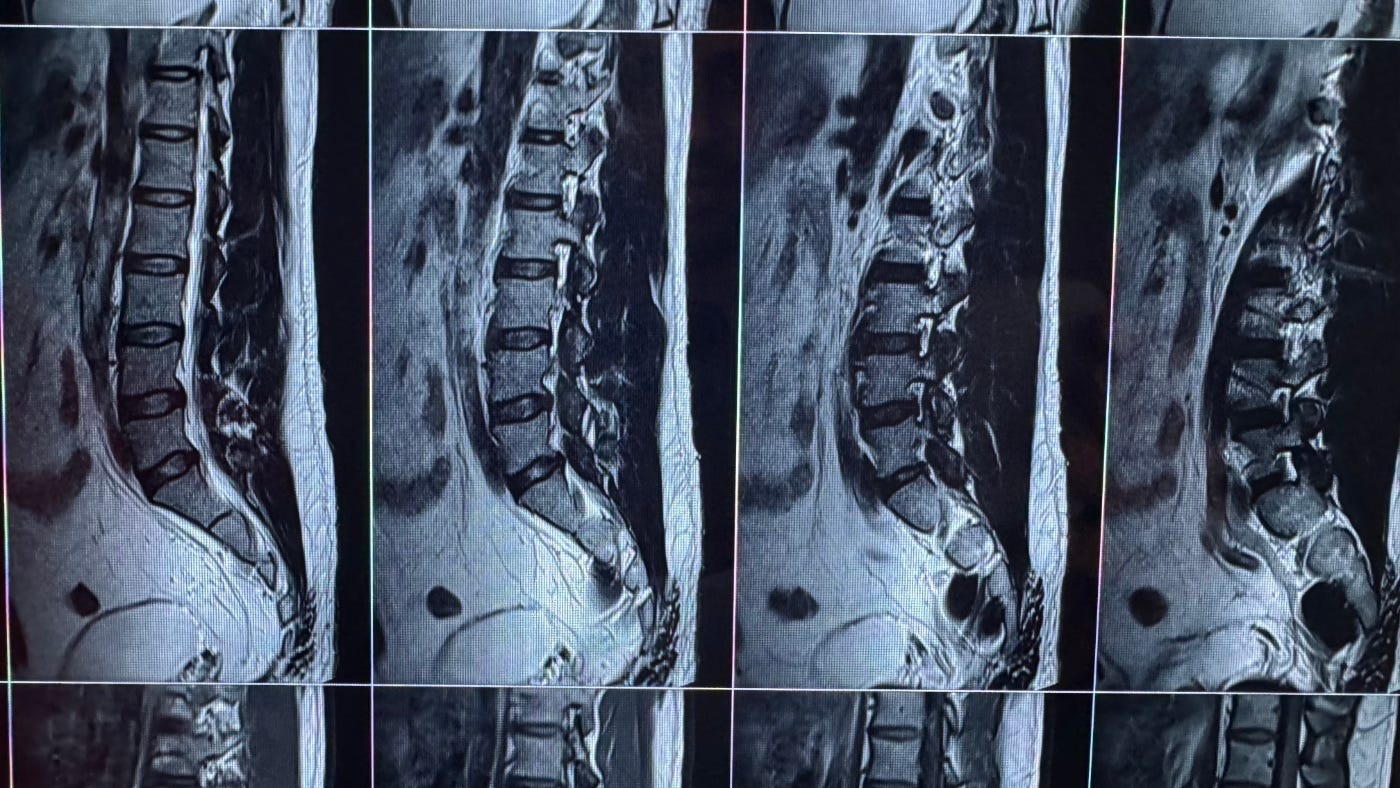

“During the remote work era, I was working from home, sitting on my bed, typing for twelve to fourteen hours a day. My back deteriorated. The pain became chronic. MRI scans showed spinal compression. I began to wonder why is my bed not like a Tesla.”